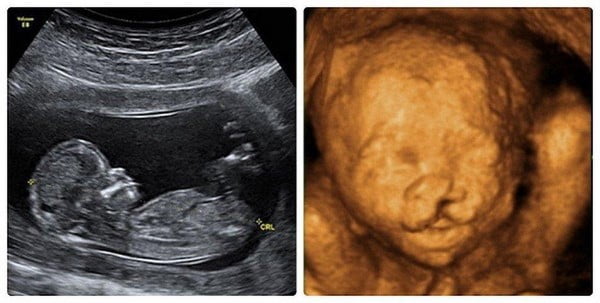

Không chỉ giúp bác sĩ phát hiện sớm những bất thường về hình thái hay sức khỏe thai nhi, siêu âm còn là khoảnh khắc xúc động – khi mẹ lần đầu nhìn thấy hình hài bé bỏng, nghe nhịp tim con đập hay thấy con mỉm cười, mút tay trong bụng mẹ.

Đây được xem là giai đoạn tối ưu để khảo sát toàn diện hình thái và cấu trúc thai nhi. Siêu âm thai hình thái ở thời điểm này có thể giúp phát hiện đa số các dị tật bẩm sinh về giải phẫu.